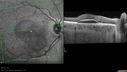

SPECTRALIS-SD-OCT SCAN: The OCT scan of the macula in the right eye does show pigment epithelium thickening, predominately inferior to the fovea where the neovascular complex is with some retinal edema there and subretinal fluid centrally. There is also excrescences off of the pigment epithelium where the white spots are, many of which are under the subretinal fluid, but there is some away from it as well. These appear to indent the small spots which are tiny, roughly 150 microns across, do appear to displace all the layers of the retina, including the external limiting membrane and the other outer lines of the retina and appear to be internal to the basement membrane of the choriocapillaris. It doesn’t appear like there is any choroidal involvement on the OCT scan. The scan of the left eye similarly shows no intraretinal or subretinal fluid. There are however, the deposits which appear to be deep pigment epithelium, but superficial to the basement membrane of the choriocapillaris putting them somewhere in the middle of Bruch’s membrane.